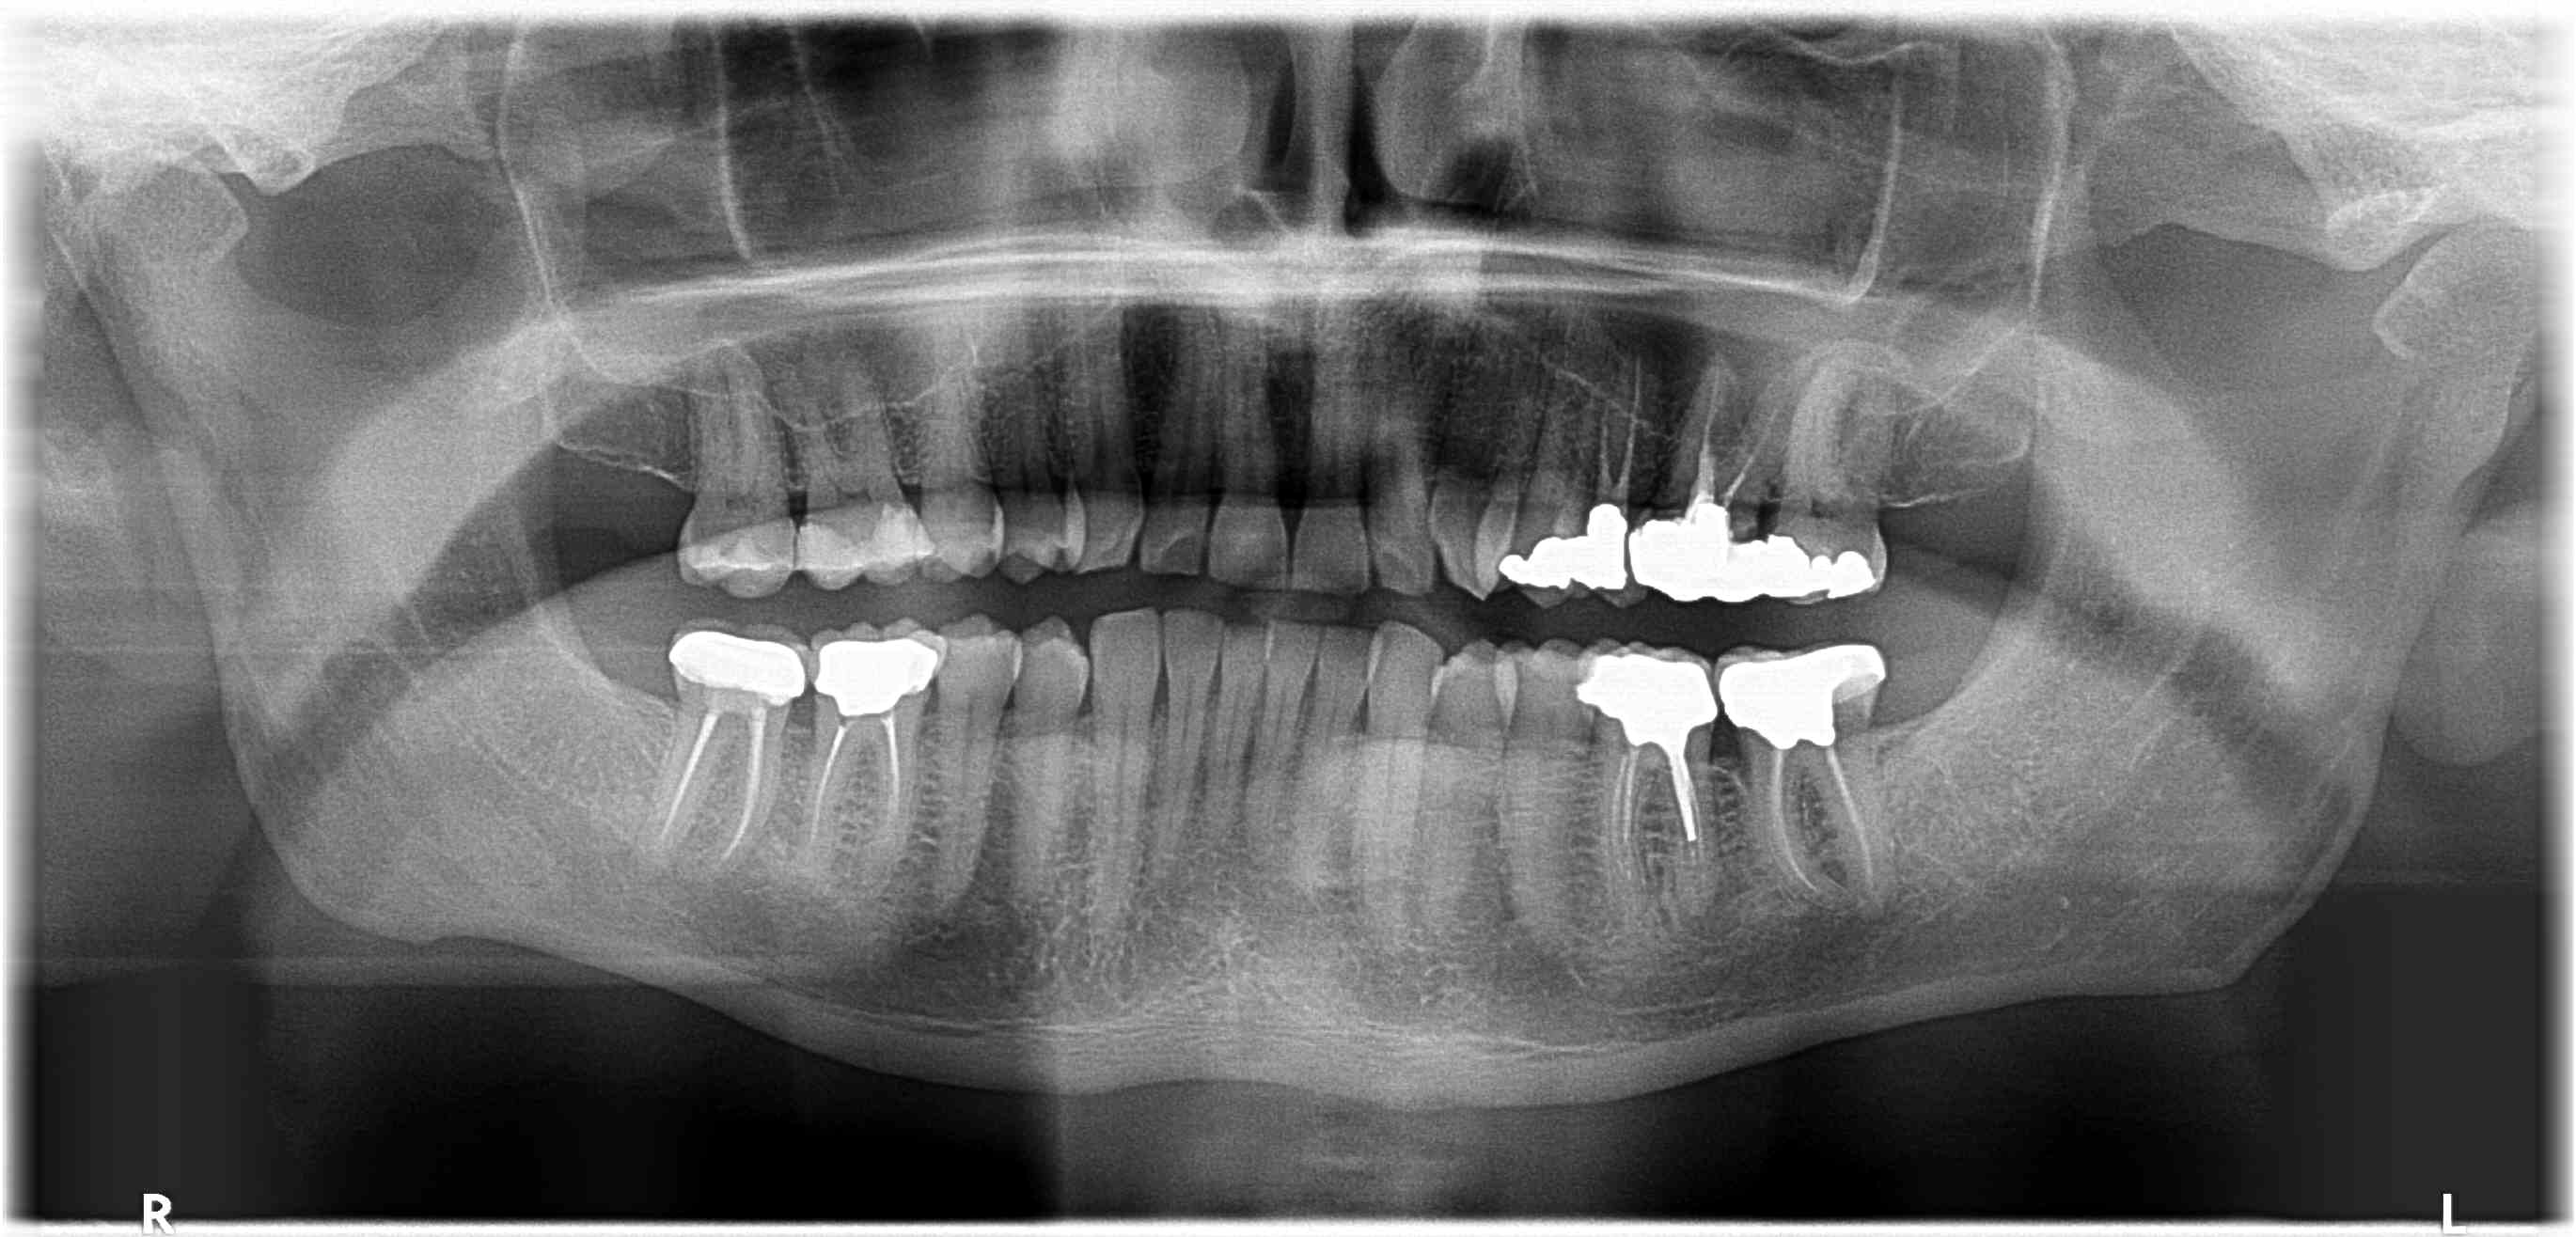

Patient 55 ans, avec claquement gauche.

la pano..

ccm refaites 36;26

salut les collègues , vous voulez quoi , une petite histoire ? ok d accord .

il a bien raison , cest dommage de s en passer . bon ça va que là c est vite vu , au regard des surfaces d usures du bloc ant sup .

- et là on constate qu il part en bout à bout d une façon symétrique , quasiment autant à gauche qu a droite .

autant dire qu il n est pas bien au centre , en oim .

- de plus quand tu vois les apophyses coronoïdes allongées , et ses angles goniaque massifs , ç est un gonz qui ne fait pas dans la dentelle question serrage , ça sent le puissant qui a fabriqué de l os réactionnel .

alors le point de départ dentaire , a mon avis est du à un sur guidage ant , lui amenant une rétropulsion mandibulaire .

bref , un sur contact ant . et effectivement , si on regarde sur la photo , le sur contact ant est symetrique .pas atonnant que son échappée d évitement ( propulsion en bout à bout ) soit symétrique aussi .

le jaune marque les 2 points et ça se voit mieux sur la photo d origine .

seulement voilà , cela ne suffit pas à le déglinger .

comme je le dis souvent , il faut tjs au moins une autre raison unilatérale , celle là , pour tirer de coté lorsqu il n est pas en propusion . un truc qui pourrait augmenter le pb du sur - guidage .

en lui décentrant son oim par exemple : pas assez qu il est esquiché vers l arriere , il se trouverait décentré en oim sur sa partie postérieur .

bref un truc qui ferait qu il n est bien ni devant ni derrière .

et ce truc je pense que ce pourrait très bien être la 37 qui ne ressemble à rien . manifestement elle a du être bien grattée le jour de la pose .

elle doit encore etre en sur occ , en tout cas on est loin loin du cuspide fosse .

donc , ce que je ferais :

1- un petit coup de bzim bzim devant , pour aligner les cretes proximales des 2 centrales avec les 2 latérales et liberer le sur contact ant , ça mange pas de pain .

2- retoucher la 37 pour le recentrer .

et là l effet devrait etre immédiat .